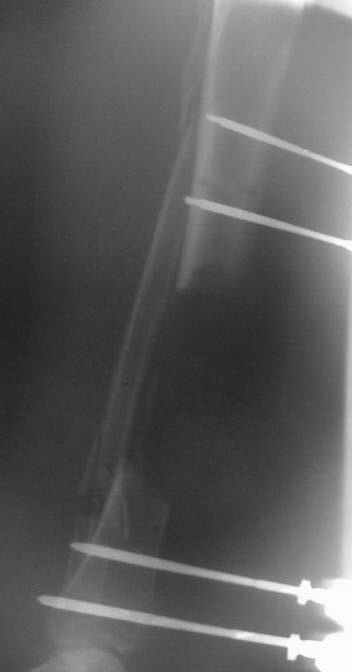

from case archives - also see Ilizarov split fibula

"fibula pro tibia" transfer for segmental tibia defects